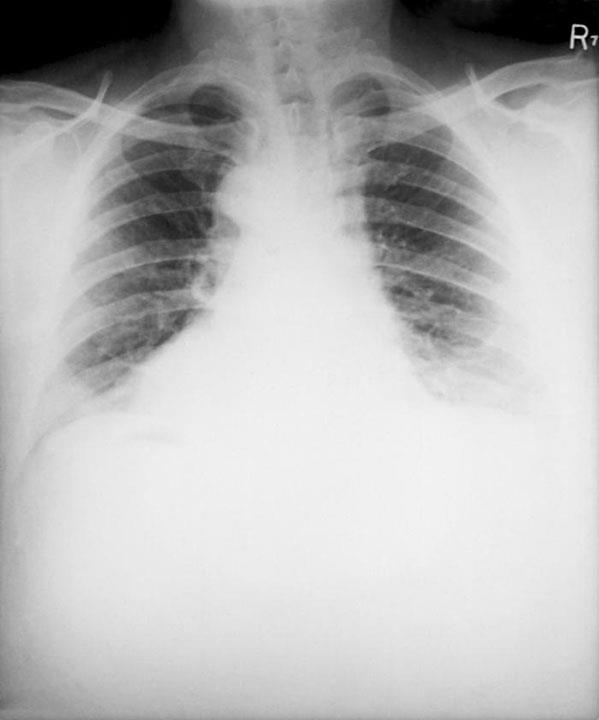

In mild cases, PE only causes shortness of breath and pleuritic chest pain. In severe cases, it can cause hypoxia, tachycardia, tachypnea, hypotension, pulmonary infarct, and death from right heart strain and arrhythmia. 11 of 61 inflight deaths undergoing autopsy after arrival to Heathrow Airport in a 1986 study died from PE: All involved flights over 6 hours.2